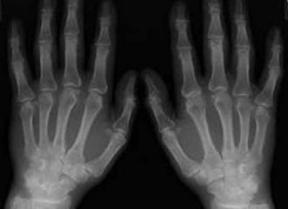

(图:治疗后的毛大爷手部X光)

陈建春主任利用中医微创可视针刀镜技术,首先清除毛大爷各关节内痛风石,缓解疼痛状况,增强关节活动能力。同时利用个性用药配合食疗调理等方案,有效降低尿酸值,并巩固治疗效果,防止病情反复发作。

经过一段时间的治疗,毛大爷手指、脚部关节内痛风石被彻底清除,关节活动能力增加,伤口愈合情况良好,无不良反应。

陈建春主任为其制定联合用药治疗方案,复查显示毛大爷血尿酸降低到402umol/L,处于正常水平。陈建春主任表示,只要毛大爷能够坚持健康饮食,就能有效康复病情,避免相关危害。